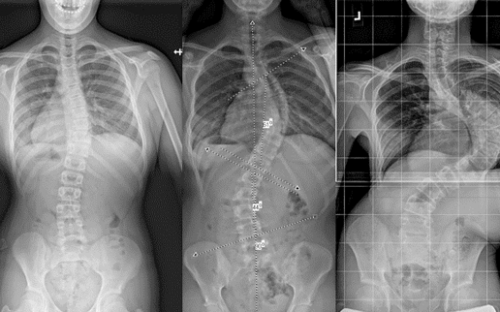

اعوجاج العمود الفقري الشديد: الخطورة في الدرجة وليس النوع

حتى الاعوجاج مجهول السبب (وهو الأكثر شيوعًا)، يمكن أن يصبح خطيرًا إذا كان شديد الدرجة.

متى يُعتبر شديدًا؟

عندما تتجاوز زاوية الانحناء 40–50 درجة

اعوجاج العمود الفقري الصدري الشديد: خطر على التنفس

من الأنواع التي تثير القلق أيضًا:

الاعوجاج الذي يصيب المنطقة الصدرية من العمود الفقري.

لماذا؟

لأن هذه المنطقة مرتبطة بالقفص الصدري

ومع زيادة الانحناء، يقل تمدد الرئتين

قد تظهر صعوبة في التنفس في الحالات المتقدمة

لهذا السبب، الاعوجاج الصدري الشديد يحتاج متابعة دقيقة، حتى لو لم يشتكِ المريض من أعراض في البداية.

هل اعوجاج العمود الفقري عند الأطفال أخطر من الكبار؟

في كثير من الحالات، نعم.

السبب:

الأطفال والمراهقون يمرون بمرحلة نمو سريع

الانحناء قد يزداد خلال أشهر قليلة

تجاهل العلاج في هذه المرحلة قد يؤدي إلى تدهور سريع

لذلك، الاعوجاج غير المعالج أثناء النمو قد يصبح أخطر من اعوجاج ثابت عند البالغين.